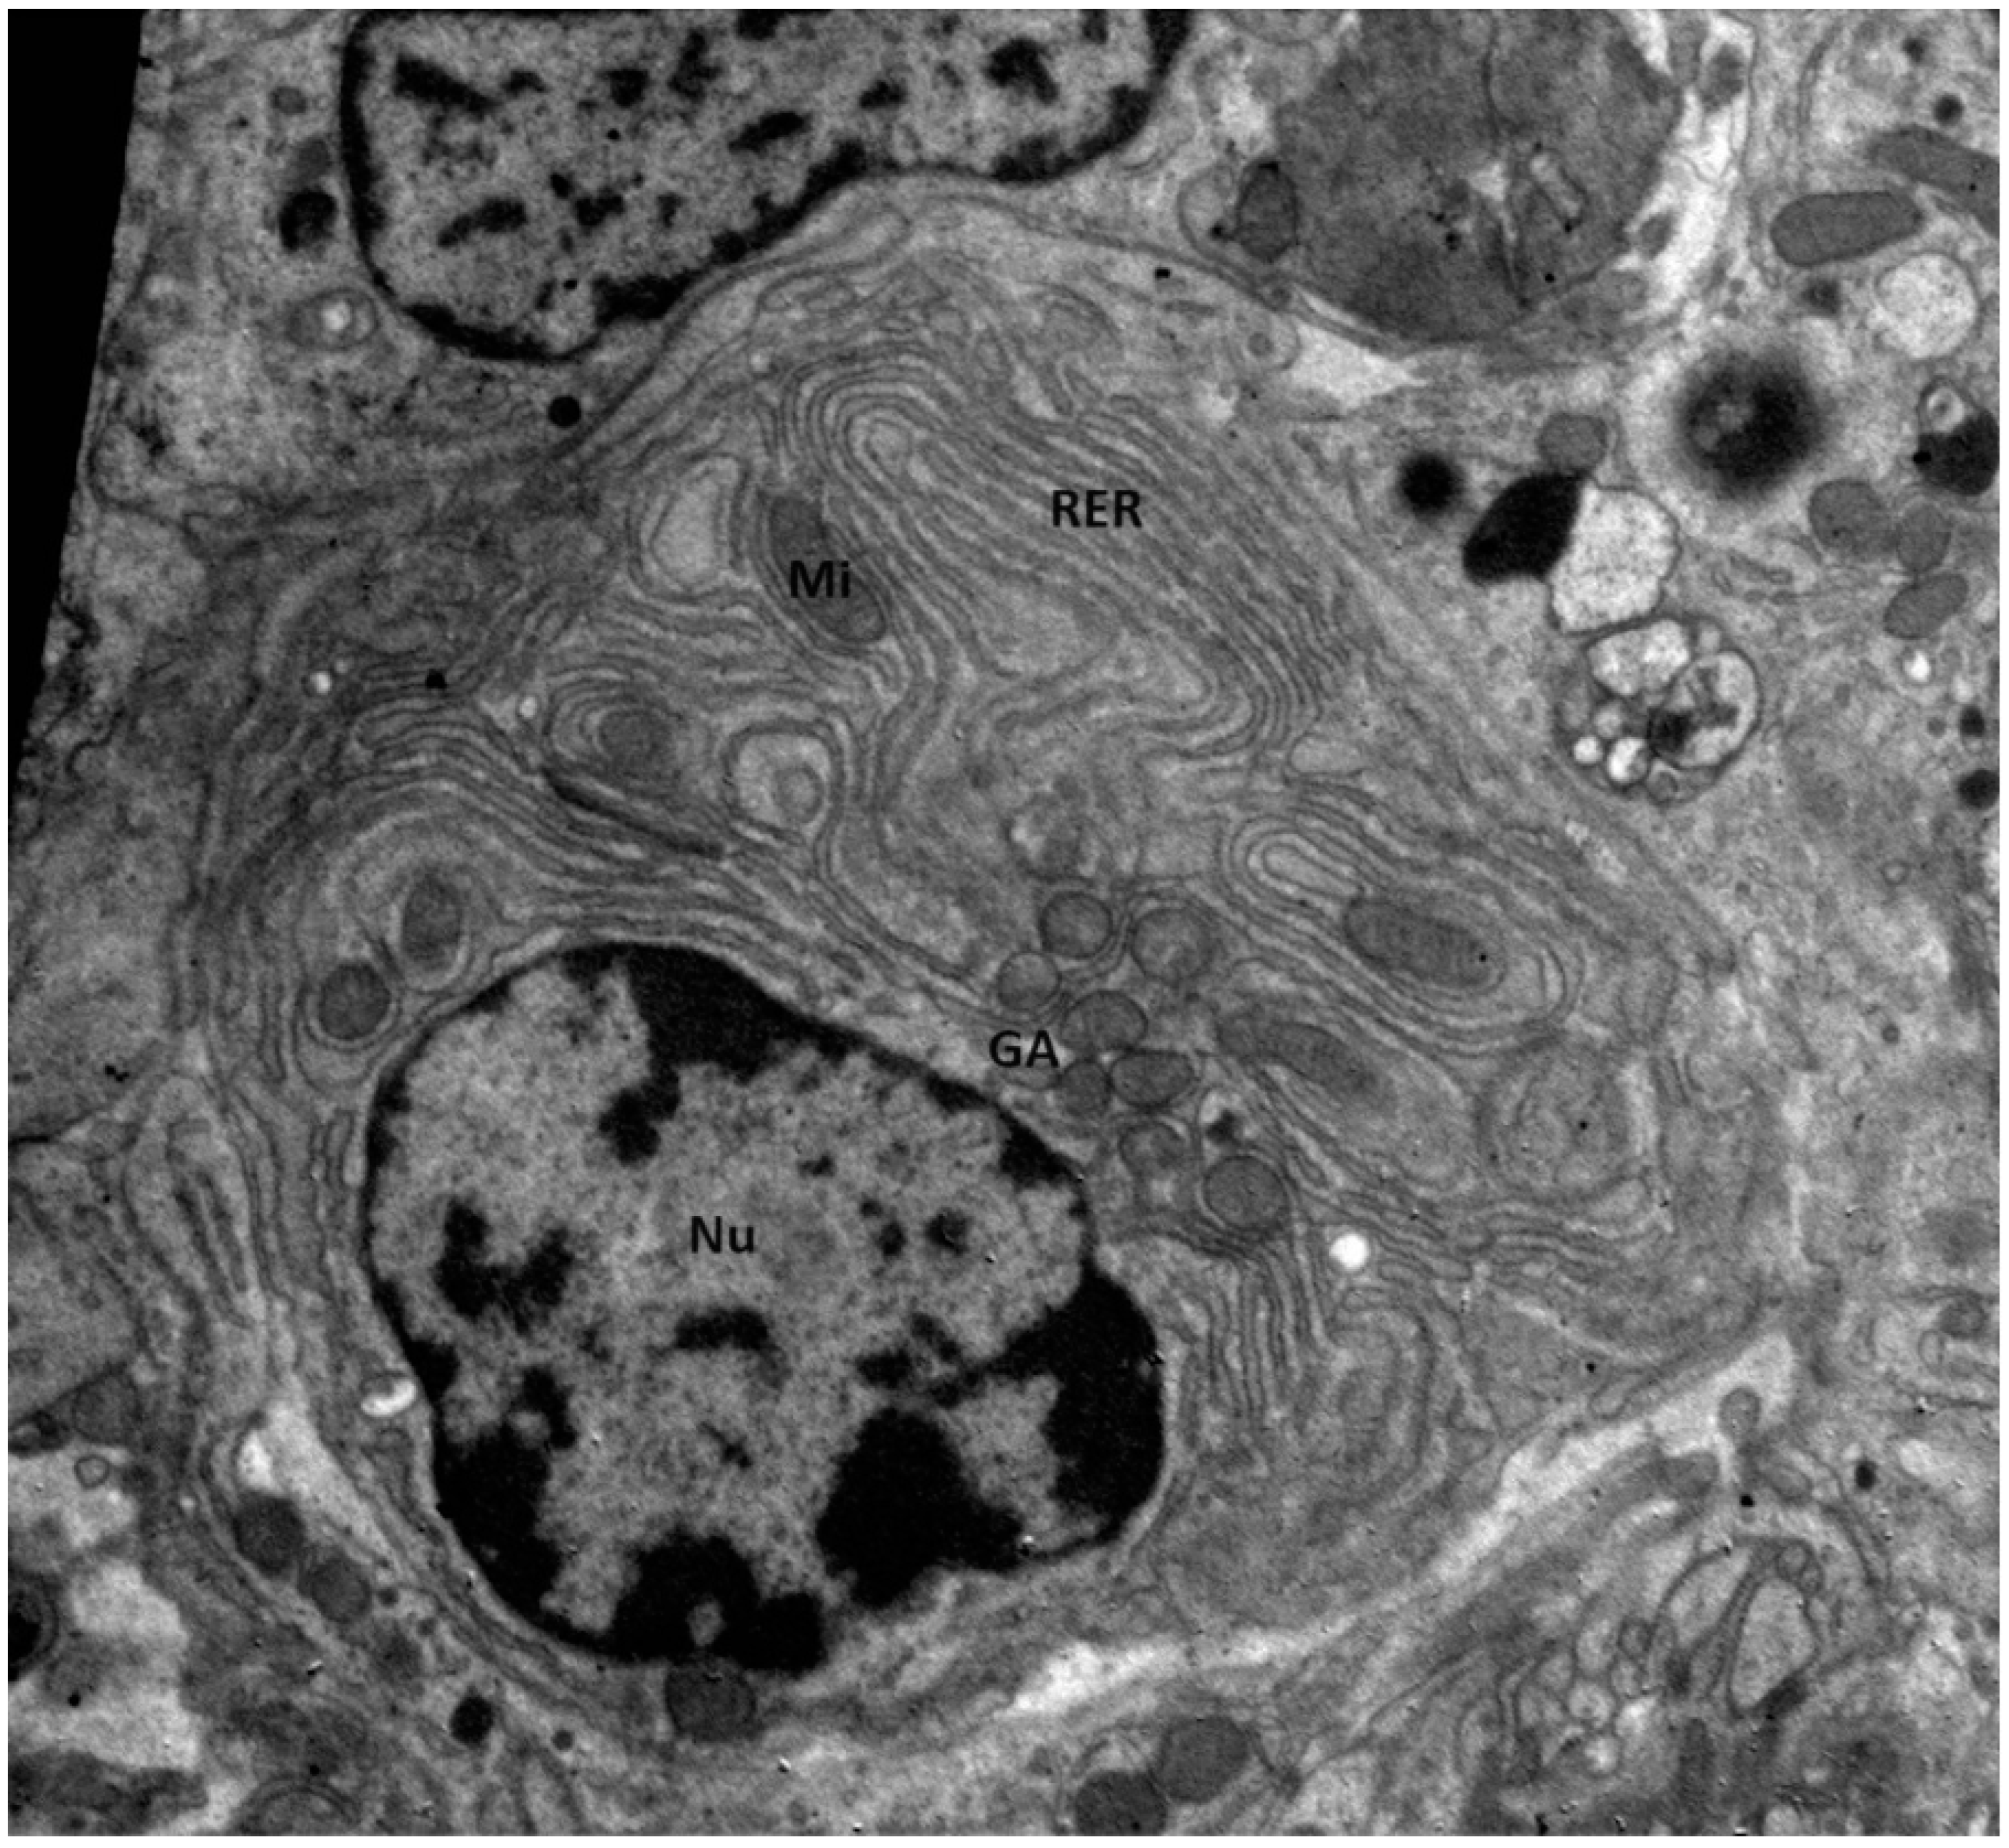

- Bassan, H.; Gutmann, H.; Djaldetti, M. Ultrastructural Characteristics of the Plasma Cells of a Patient with Nonsecretory Myeloma and Plasma Cell Leukemia. Acta Haematol. 1981, 66, 129–133. [Google Scholar] [CrossRef]